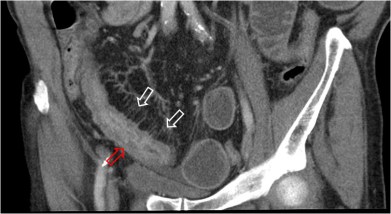

SIGNO DEL SANDWICH

Signo de linfoma abdominal tanto en la TC como en ecografía. Consiste en la presencia de masas adenopáticas que rodean y desplazan la arteria y la vena mesentéricas superiores sin comprimirlas.

La fotografía corresponde a un paciente con linfoma (flecha roja) que forma conglomerados adenopáticos que respetan los vasos mesentéricos (flecha blanca).

Por extensión, se puede emplear este signo en conglomerados linfomatosos que rodean pero respetan otras estructuras vasculares diferentes de los vasos mesentéricos, como vemos en el ejemplo siguiente con las arterias renales.